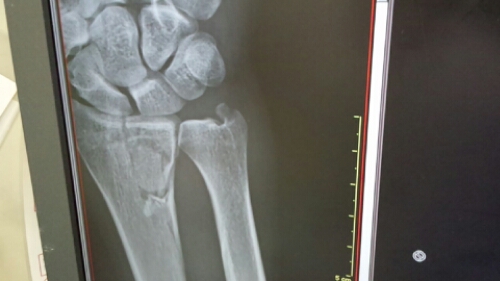

移動して間もなく腕に硬いものを巻かれることになった。